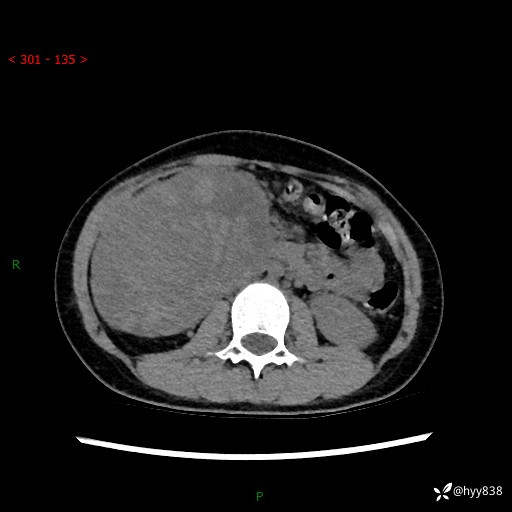

性别:女

年龄:13岁

简要病史:超声提示上腹部巨大包块

上腹部CT平扫